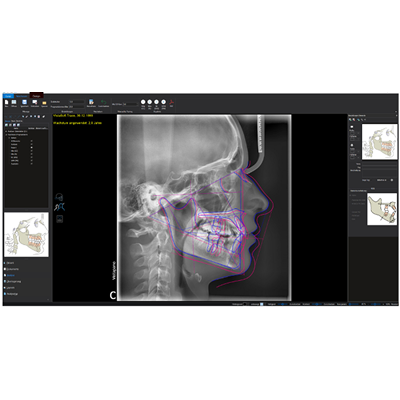

Our software module VistaSoft Trace simplifies the way in which orthodontists can carry out their cephalometric assessments and draw up treatment plans. Discover how VistaSoft Trace can help you to streamline practices in your surgery and increase patient satisfaction at the same time. Optimise work processes and set new standards in orthodontics!

Cephalometric analyses

With the aid of innovative and extensive tools using artificial intelligence, cephalometric analyses can be completed within a few seconds using VistaSoft Trace. This user-friendly software add-on identifies reference points and soft tissue silhouettes automatically and plots them on the X-ray image.